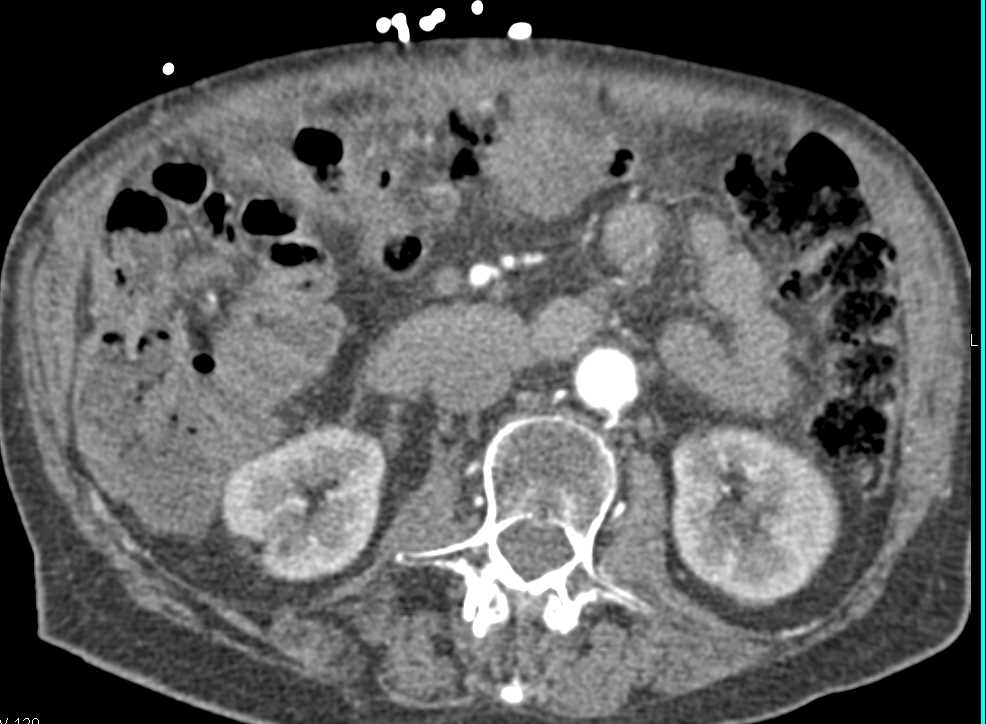

Exophytic Gastric GIST Tumor